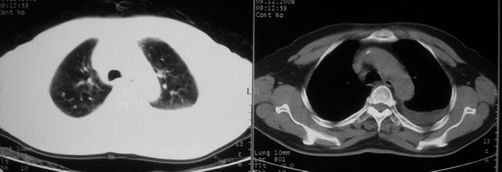

男,78岁,咳嗽、咳痰、发热入院,抗炎治疗一周后已退热,咳血似痰。

10月9日片: